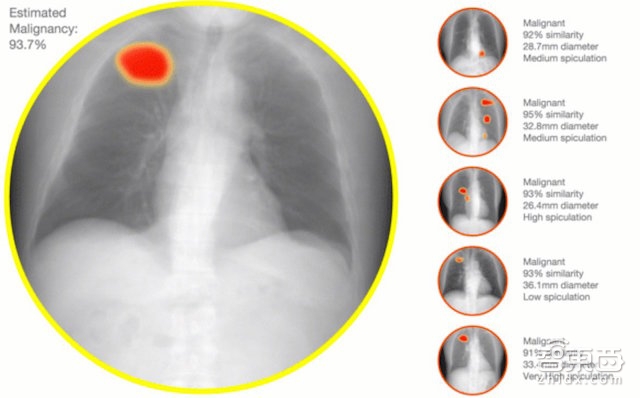

下一步,医拍智能将业务拓展至拓CT、X光、病理切片等医疗影像的识别与诊断。医拍智能医学影像AI系统结合了最新的深度学习算法,在人类医生的帮助下,通过对大量医疗图像数据进行解析,自动总结出能够代表恶性肿瘤的“形状特征”以及形成能够用来判断有无恶性肿瘤的“识别模式”。AI系统将其总结出的识别模式应用于医学影像中时,便可判断影像中是否存在恶性肿瘤,且准确度和判断速度超越了传统方式。